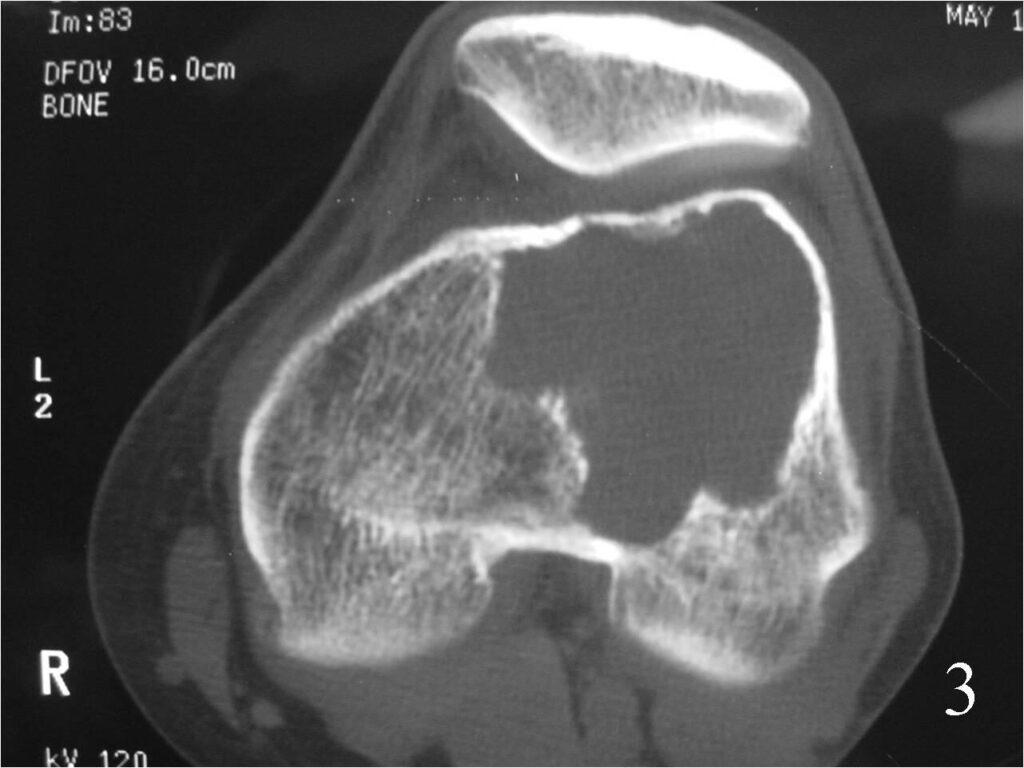

CT useful for demonstrating absence of mineralization and for showing internal trabeculations as well as a subtle periosteal reaction that may exist around any soft tissue component (Fig. 3)

Fig. 3 Axial CT reconstruction of distal femur demonstrating an eccentric geographic lesion well circumscribed.